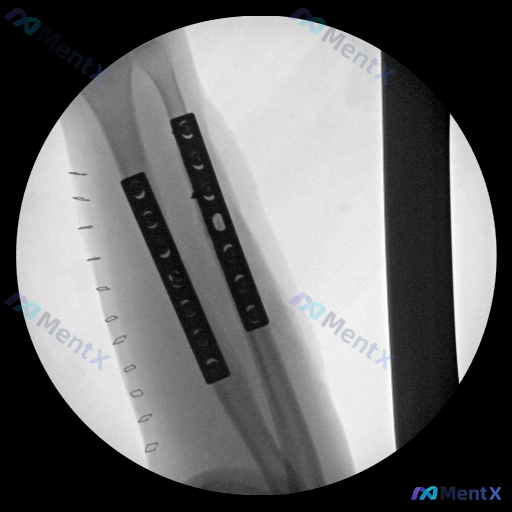

整理到一张小腿部位的影像学资料,是圆形视野,看起来像是术中或术后的透视影像。 目前可见的表现大概整理如下: - 显示的是胫骨与腓骨的骨干段,都有金属内固定钢板(接骨板)覆盖,能看到螺孔,钢板跨越了可能的骨折或手术区域 - 钢板覆盖区的骨皮质轮廓连续性看起来尚可,没有明显的骨折线延伸到钢板外,但金属伪...